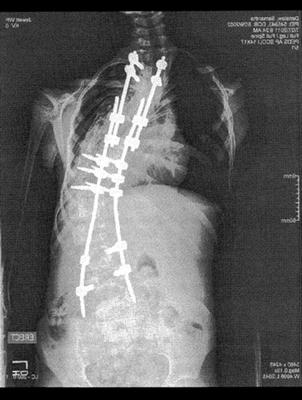

Nothing has worked and so her last surgery was to remove some of the old hardware (first pic), insert adjustable rods and to fuse most of her vertebra.

Her back, hips, rib cage etc. are still "off" and there are pulmonary issues due to the abnormal growth of her rib cage due to the scoliosis. She is restricted physically (no phys Ed, for example) and has allowances to use the elevator at school, instead of the stairs. She uses a roller backpack and has other accommodations.

I've include a couple of X-rays to give you an idea of Sam's situation. If you have any suggestions, recommendations etc. regarding chiropractic treatment for Sam I would appreciate it.

Whilst it's not conclusive, because it would appear the x-rays were taken lying down, is that Sam may have a severely short leg. Has there ever been mention of this, and is she wearing a lift in her shoe? It could make a huge difference.

You are right. A scoliosis of this nature, and the short leg causing it, in part let it be said, will have profound affect on other joints in her neck, but also in the hip and knee. These peripheral problems also need to be addressed.